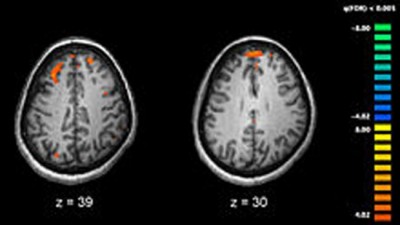

Social awareness increases prove brain changing in adults with autism

Mar 30, 2018, at 09:27 pm

Dallas, Mar 30 (IBNS): Researchers at the Center for BrainHealth at The University of Texas at Dallas, in collaboration with co-leading authors at George Washington University and Yale, have demonstrated in a pilot study that a clinician-driven virtual learning platform, tailored to young adults on the autism spectrum, shows improved social competency.